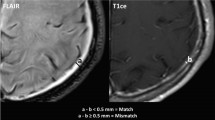

The 3D-real IR and MRC images, with anonymized patient information, were imported into Fiji/ImageJ software version 1.53a (NIH, Bethesda, USA). A smooth filter was applied to the 3D-real IR images to exclude small areas of high signal intensity, such as the brain cortex boundaries. These images were then binarized to allow the measurement of leaking GBCA under narrow window conditions (width = 2, level = 30; Fig. 1a). The window level and width parameters were chosen based on a previous study [6]. The MRC images were also binarized to identify the areas where CSF was present under narrow window conditions (width = 2, level = 180; Fig. 1b). Averages (Fig. 1c) were calculated between these two types of binarized images. The slices above the lateral ventricles were extracted to quantify the voxels exhibiting GBCA leakage into the CSF (hereafter named V-leak).

a A 3D-real inversion recovery image binarized to measure Gadolinium-based contrast agent leakage under narrow window conditions (width = 2, level = 30). b A magnetic resonance cisternography image binarized to identify areas where cerebrospinal fluid was present under narrow window conditions (width = 2, level = 180). c Average image between these two types of binarized images to calculate the number of voxels indicating leakage of Gadolinium-based contrast agent into the cerebrospinal fluid